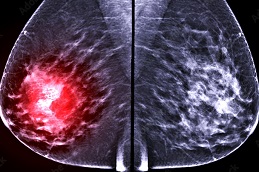

Breast Cancer Screening is a low-impact, preventive testing approach formulated to identify the breast-associated abnormalities in early stages to prevent them from getting worse, thus promoting breast health.

If screening is conducted by employing the latest 3D mammography or MRI, it appears to be usually pricey as compared to standard mammograms.